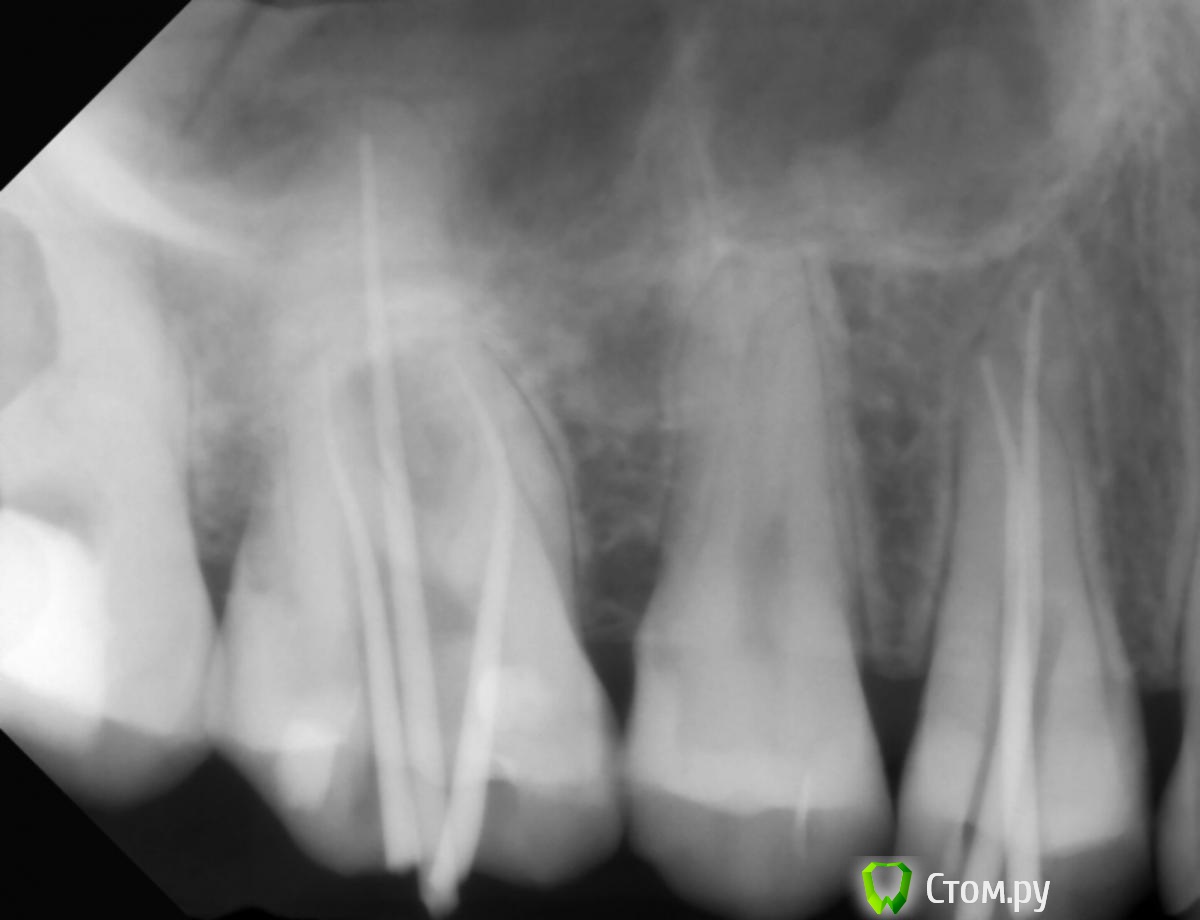

Юлия Арт Опубликовано 13 марта, 2014 Автор Поделиться Опубликовано 13 марта, 2014 вот фото, панорамный сделали сегодня (вторая кист куда-то делась у верхней 5-ки, вырывать зуб не стали),троица с депульпцией болит и ноет сильно, есть на них не могу Ссылка на комментарий

anvladd Опубликовано 13 марта, 2014 Поделиться Опубликовано 13 марта, 2014 17 зуб похоже проблемный уж слишком пломба глубоко. Ссылка на комментарий

Л Ю С Я Опубликовано 13 марта, 2014 Поделиться Опубликовано 13 марта, 2014 1.4 перелечивать, разобраться с 1.7 и 1.5, возможно и 1.6 проблемный Ссылка на комментарий

anvladd Опубликовано 13 марта, 2014 Поделиться Опубликовано 13 марта, 2014 Нерв удалили в 16 а вот 17 судя по снимку под подозрением. И как писала доктор выше 14 перелечивать каналы. Ссылка на комментарий

anvladd Опубликовано 13 марта, 2014 Поделиться Опубликовано 13 марта, 2014 уважаемые, уже третий день после начала депульпации 7, 6(завершено) и 4-го верхних болит вся цека и все зубы 7-6-5-4...есть на них не могу, такое ощущение что их распирает изнутри, если стучать по ним-небольно, но есть неокторые места куда если пища попадает или пальцем надавить - стреляет больно! через 2 недели только приём у врача на завершение депульпации... а я ждать не смогу, отнимается левая верхняя сторона. судя по фото, что там может быть? или нервы в зубах или , может, они поломаны или десна воспалены? воможности КТ сделать пока неттак потому и болит что,как я понимаю,не завершена депульпация 7 и 4 зубов. Вы вложили снимок до или после депульпации, напишите. 1 Ссылка на комментарий

Юлия Арт Опубликовано 14 марта, 2014 Автор Поделиться Опубликовано 14 марта, 2014 так потому и болит что,как я понимаю,не завершена депульпация 7 и 4 зубов. Вы вложили снимок до или после депульпации, напишите.всё верно понимаете, у 6-го каналы вроде почистили, хотя я тут начиталась что их там 4-ре, врач нашёл только 3. 6-й тоже болит сильно, они вообще все с 7-го по 4-й дружно ноют и стреляют. скорее всего там не просто пульпит был, но и периодонтит судя по моим симптомам Ссылка на комментарий

anvladd Опубликовано 14 марта, 2014 Поделиться Опубликовано 14 марта, 2014 тогда долечивать 7,4 и перелечивать 6,искать 4й канал. удачи. Ссылка на комментарий